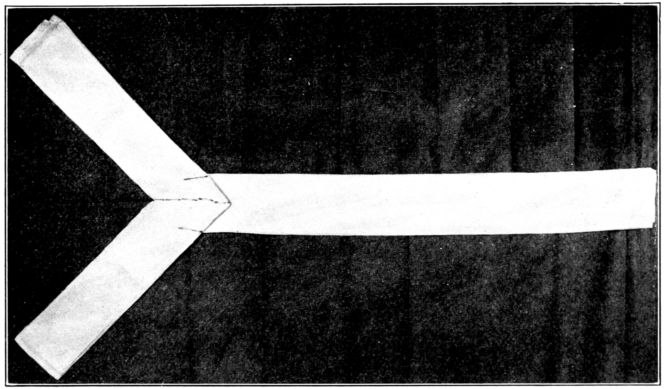

| 124. | Y binder before application | 345 |

| 125. | Y binder applied | 346 |

| 126. | The same seen from the other side | 347 |